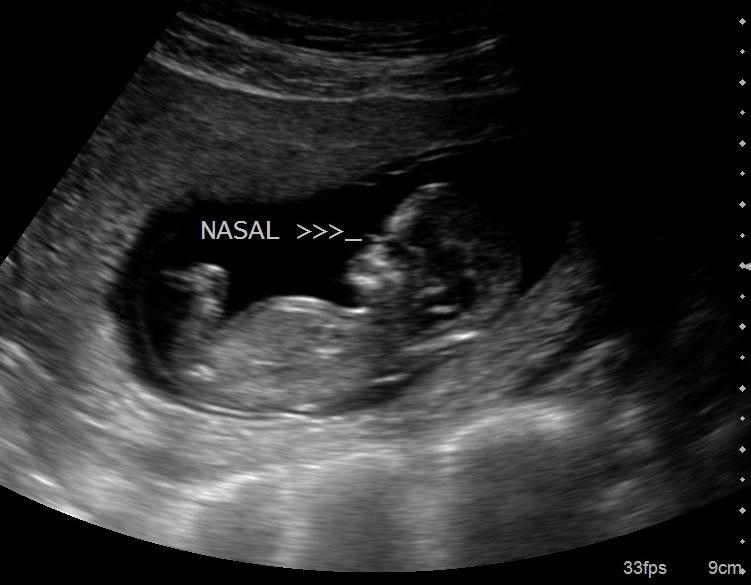

I think I might see a nub in the 2nd pic, the one with the word "nasal" on it. If that's the nub, then I'd say girl.